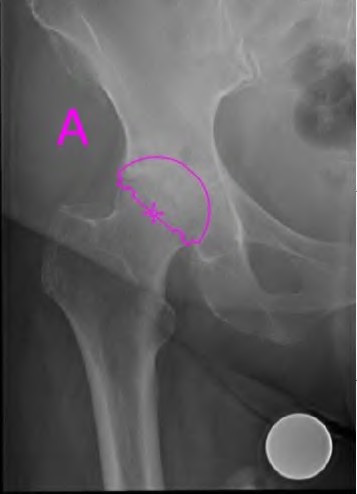

A 45-year-old female with developmental dysplasia of the hip (DDH) presents for THA. Preoperative radiographs show the femoral head is subluxated, with 80% proximal migration relative to the height of the normal true acetabulum. Based on the Crowe classification, what type of dysplasia does she have?

Explanation